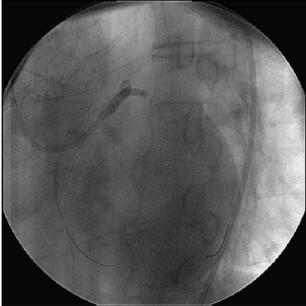

图058‐4 导丝进入LAD、LCX 远端

L AD 行PCI 术(图058‐4~图058‐7):送入7F XB 3﹒5 指引导管至左冠口,根据此前造影影像,循管送入Runthrough NS 导丝至LAD 远端,再送入Fiel der 导丝至LCX 远端,沿L AD导丝送入1.5mm×15mm 球囊(Ryujin)定位于LAD 中段病变处,以20at m×20s 多次扩张,循管送入2.5mm×33mm 药物支架(Firebird 2)定位于LAD 中段病变处,以(8~10)at m×10s释放,复查造影见病变覆盖良好,局部无残余狭窄,再送入3.0mm×13mm 药物支架(Firebird 2)定位于LAD 中段病变处,以18at m×180s 释放,两支架部分重叠,复查造影见病变覆盖良好,局部无残余狭窄,沿LAD 导丝送入3.0mm×18mm 药物支架(Firebird 2)定位于LAD 近中段病变处,以18at m×20s 释放,复查造影见病变覆盖良好,局部无残余狭窄,再送入3.5mm×29mm药物支架(Firebird 2)定位于L AD 开口后,以12at m×16s 释放,复查造影见病变覆盖良好,局部无残余狭窄,循管送入另一条Runthrough NS 导丝替换原LCX 导丝,沿LCX 导丝送入3.5mm×23mm 药物支架(Firebird2),支架跨越L M‐LCX 病变,以(12~14)at m×14s 释放,支架球囊定位于支架前后,以(12~14)at m×18s 多次后扩张,沿LAD 导丝送入4.0mm×12mm 球囊(Monorail),沿LCX 导丝送入3.5mm×12 mm 球囊(Monorail),同时以12at m 行Balloon Kissing 两次,复查造影(图058‐8~图058‐10)见病变覆盖良好,局部无残余狭窄,远端血流TI MI 3 级。